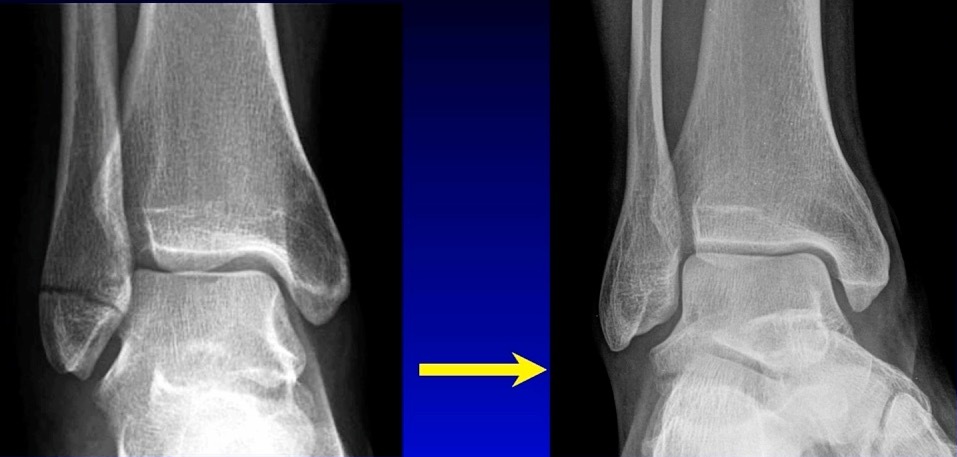

We don’t necessarily operate on all ankle fractures. The following x-ray demonstrates a stable ankle fracture (Figure 1).

This patient can start immediate, protected, weight bearing in a boot or air cast. If you’re not practicing that, you should! I still see elderly patients with a small “crack” like this, that are kept non-weight bearing for two months. Don’t do that! These are stable injuries. They can start immediate, protected, weight bearing in a boot, and can wean out of the boot as tolerated.